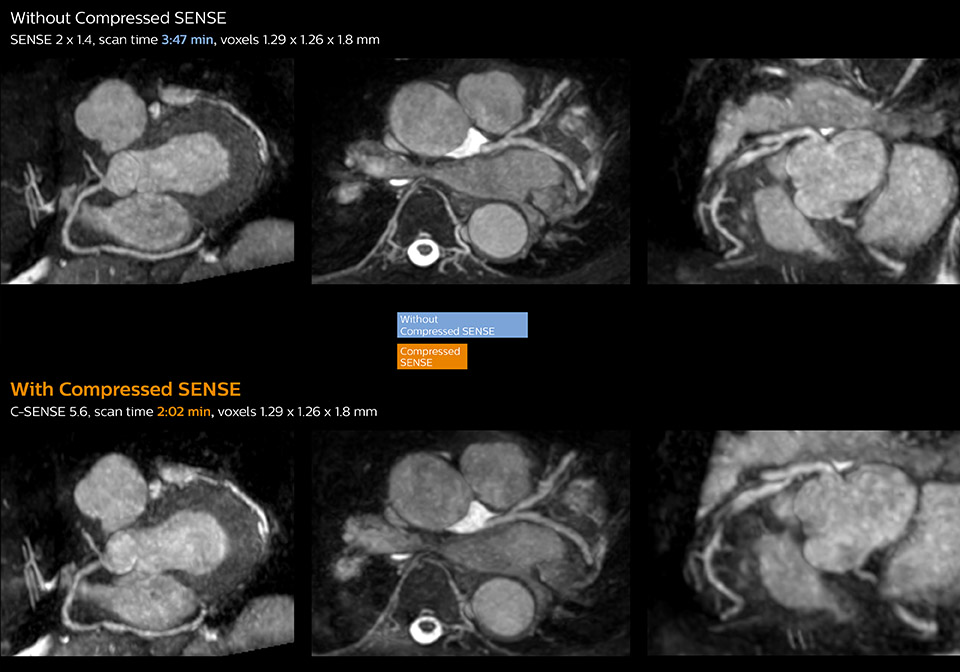

“Compressed SENSE has now been implemented in all cardiac exams. Thanks to the acceleration, fewer breath holds are now needed, or breath hold times are shortened. This reduces the burden of the exam for cardiac patients, without affecting the quality of information required for cardiac function analyses,” he says. “Because it’s easier for patients to comply with the breath hold times” “In our previous cardiac cine sequence, we were acquiring two slices during one breath hold. With Compressed SENSE, we increased this to four slices per breath hold. It is also possible to shorten scanning time using a C-SENSE factor 6 without sacrificing image quality.”

Dr. Koshi Miyake, cardiologist, explains that scanning of patients with cardiac arrhythmia can be challenging, as scanning times can become very long due to the varying heart rate. So his most important motive to implement Compressed SENSE in cardiac MRI exams was to reduce the burden of breath holds for the patient, while maintaining high image quality. He hopes this can also help to reduce motion caused by the difficulty for patients to hold their breath.

“Typically, in scans with high contrast, such as 2D balanced TFE cine, a quite high C-SENSE factor may be used. When we tried a higher C-SENSE factor, we saw still no significant influence on cardiac ejection fraction, but 2D image quality started to decline. For coronary imaging, we use a C-SENSE factor of 3 in 3D balanced TFE, or even up to 4 when contrast is high.”

These images of a patient with acute myocardial infarction images were acquired on Ingenia 1.5T with and without Compressed SENSE.

These images with and without Compressed SENSE were acquired on Ingenia 1.5T.